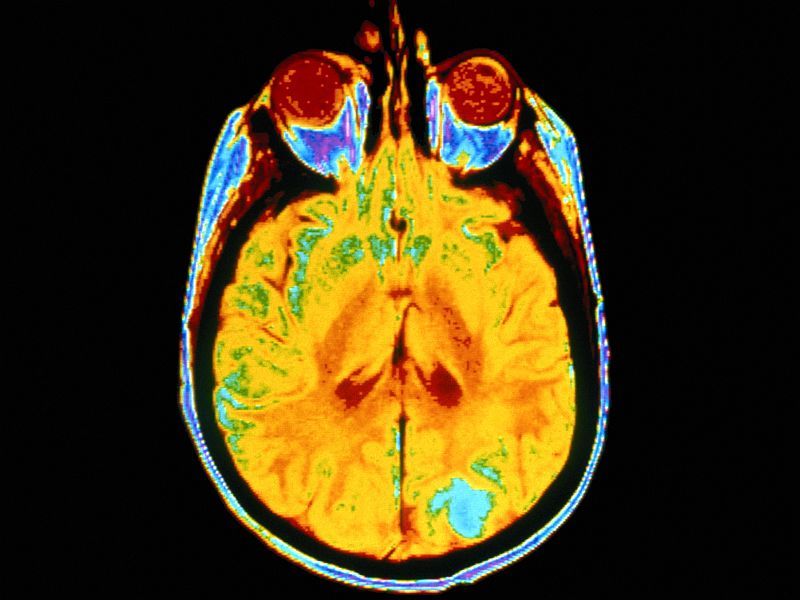

THURSDAY, May 6, 2021 (HealthDay News) — A deep learning model is feasible for differentiating normal or likely abnormal brain magnetic resonance imaging (MRI), according to a study published online April 21 in Radiology: Artificial Intelligence.

Romane Gauriau, Ph.D., from the MGH & BWH Center for Clinical Data Science in Boston, and colleagues conducted a retrospective study to develop a deep learning approach using T2-weighted fluid attenuated inversion recovery (FLAIR) images to classify brain MRI as likely normal or likely abnormal. A convolutional neural network was trained on a large heterogeneous dataset covering a broad range of pathologies. Data were included from three datasets: Dataset A included 2,839 patients; dataset B included 6,442 patients; and dataset C included 1,489 patients. Datasets A and B were split into training, validation, and test sets, while dataset C was only used for testing.

The researchers found that the F1-score was 0.72 for model A, which was trained on dataset A from one institution and tested on dataset C from another institution; when compared with findings from the radiologic reports, the area under the curve was 0.78.

“The problem we are trying to tackle is very, very complex because there are a huge variety of abnormalities on MRI,” Gauriau said in a statement. “We showed that this model is promising enough to start evaluating if it can be used in a clinical environment.”